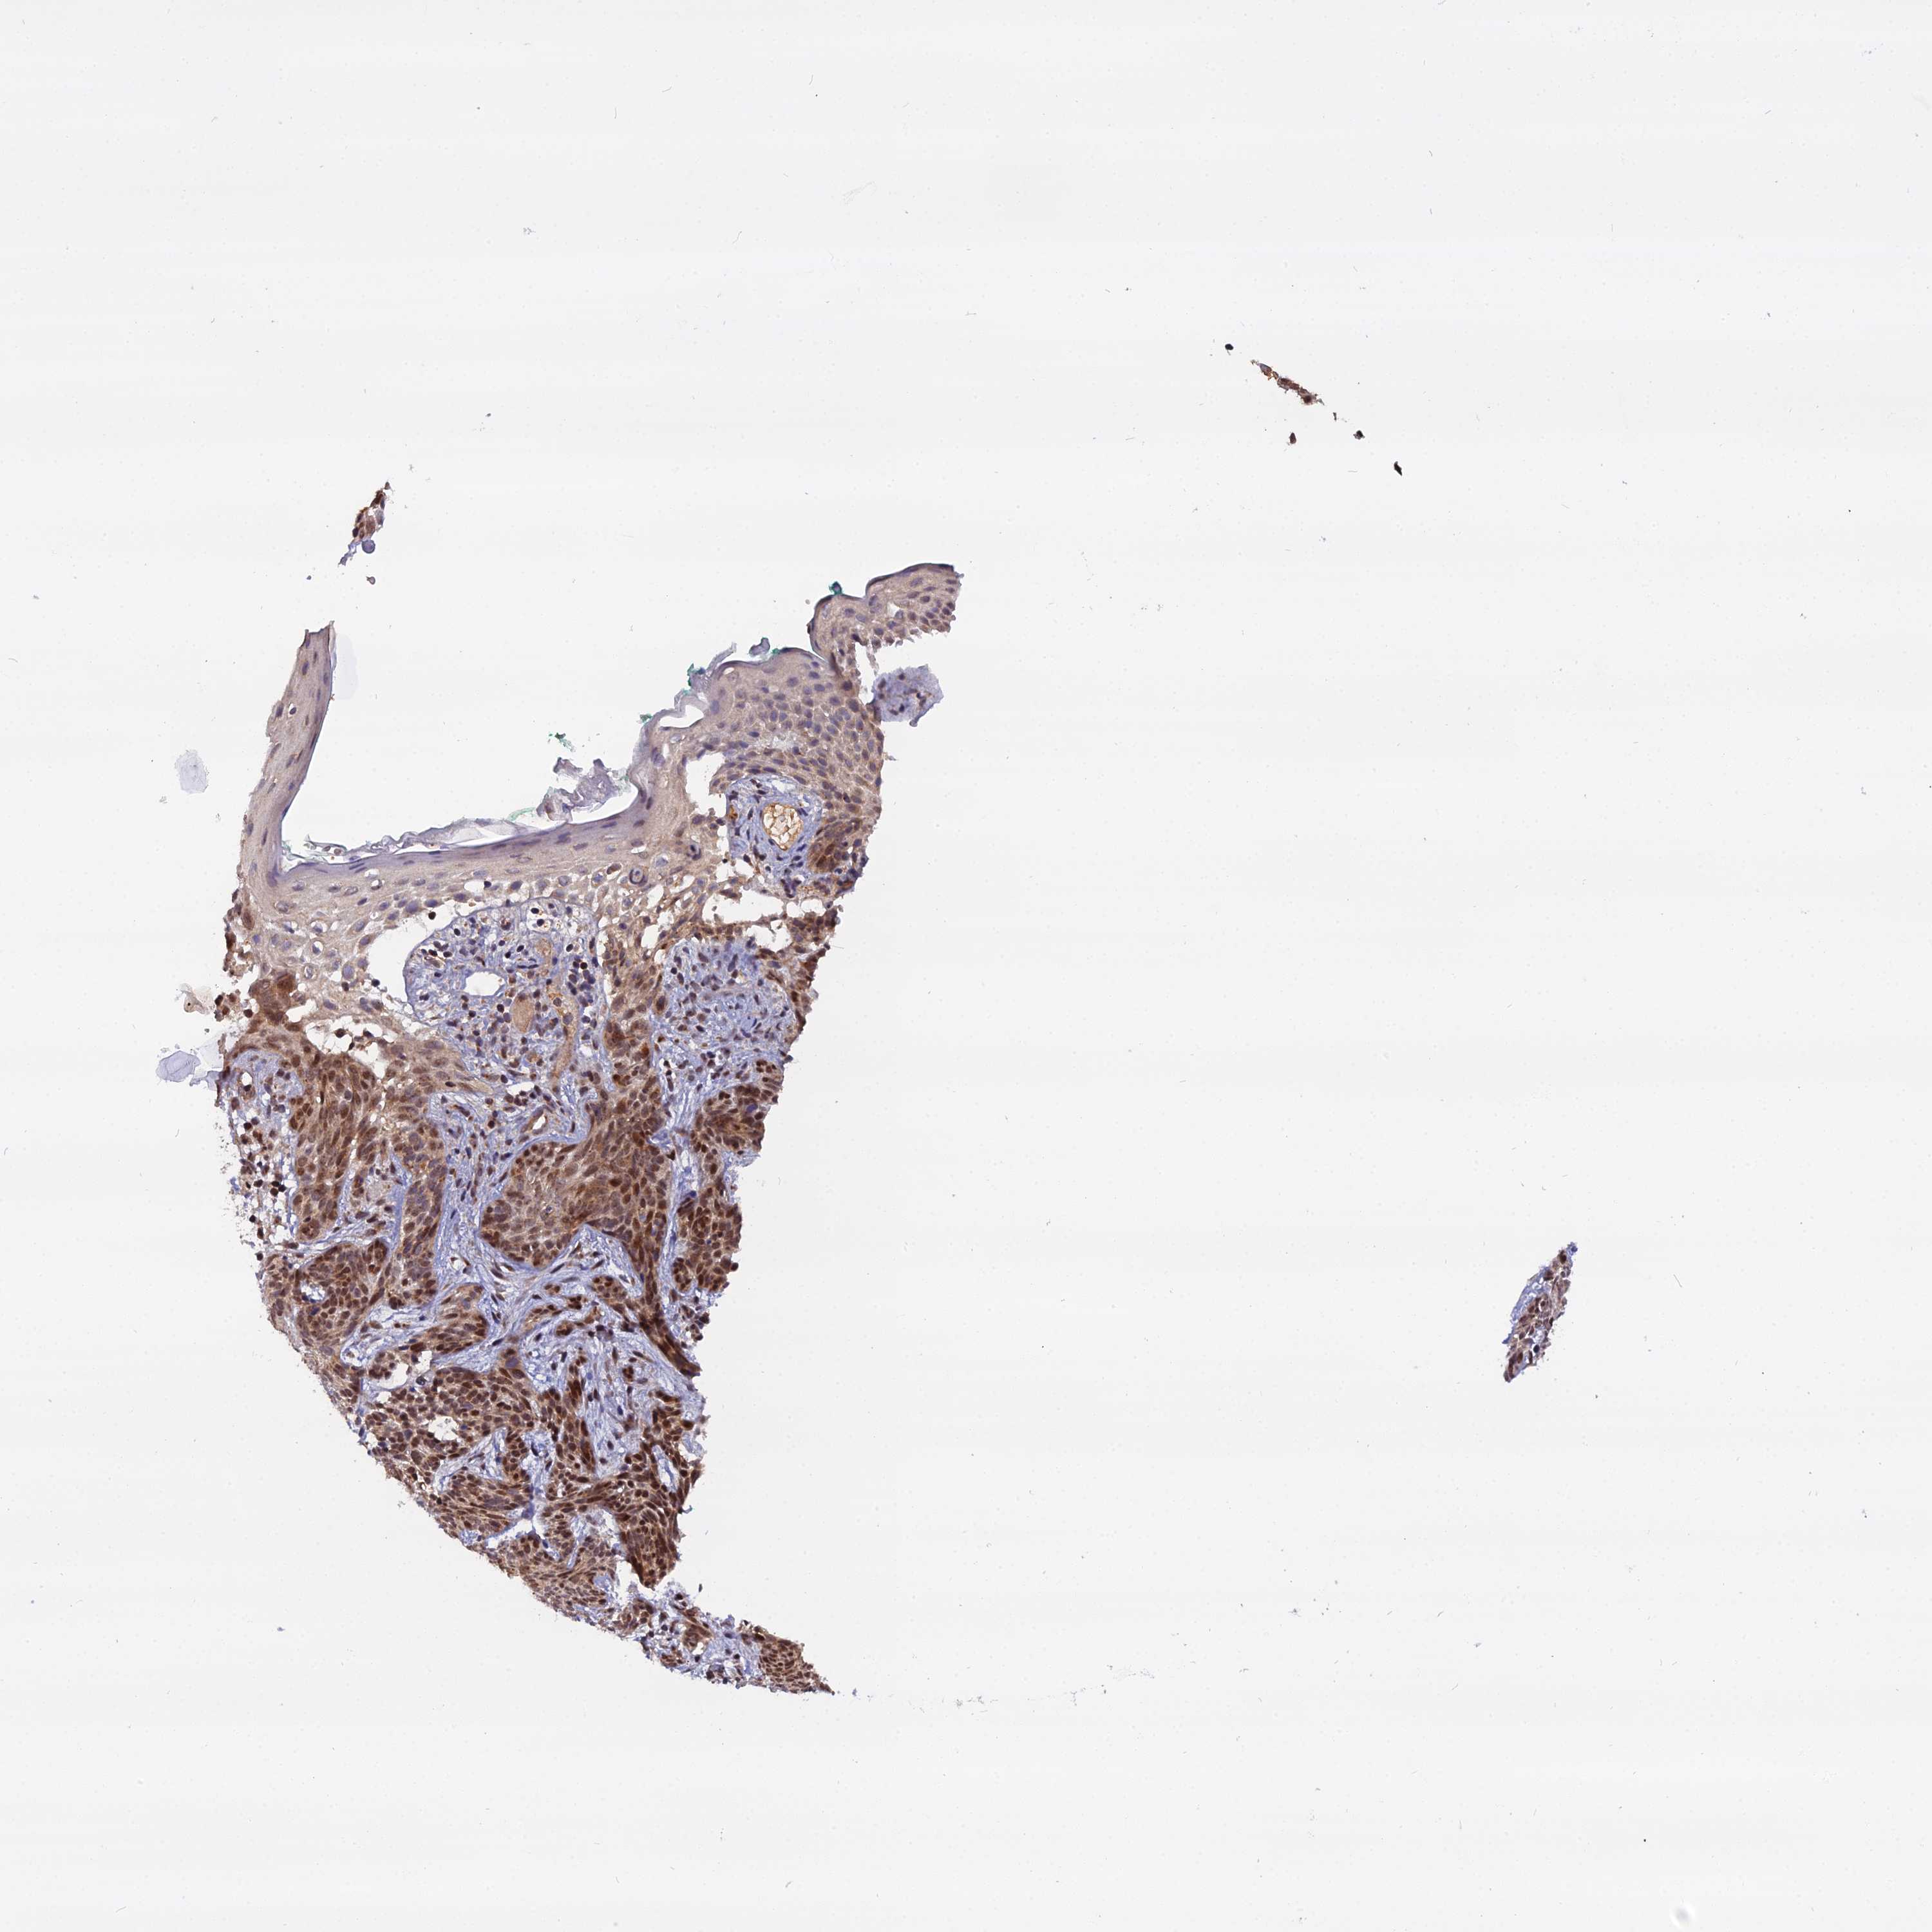

Basal cell and squamous cell cancer

SKIN CANCER - Protein expressioni

A mouse-over function shows sample information and annotation data. Click on an image to view it in a full screen mode. Samples can be filtered based on level of antibody staining by selecting one or several of the following categories: high, medium, low and not detected. The assay and annotation is described here.

Each image is clickable and will lead to virtual microscopy that enables deeper exploration of all samples and also displays staining intensity scores, fraction scores and subcellular localization as well as patient and tissue information for each sample.

Antibody HPA044610

Staining

High

Medium

Low

Not detected

Intensity

Strong

Moderate

Weak

Negative

Quantity

>75%

75%-25%

<25%

None

Location

Nuclear

Cytoplasmic/membranous

Cytoplasmic/membranous,nuclear

Basal cell carcinoma